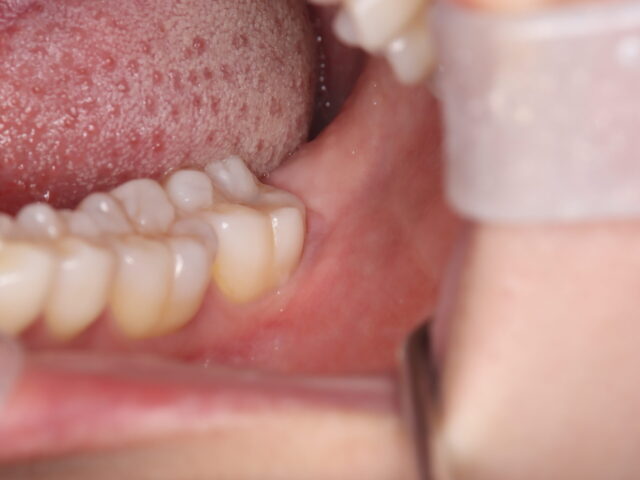

術前

左下第一大臼歯(6番目の歯)、第二大臼歯(7番目の歯)が並んでいる様子。

親知らず(8番目の歯)は見えていない。